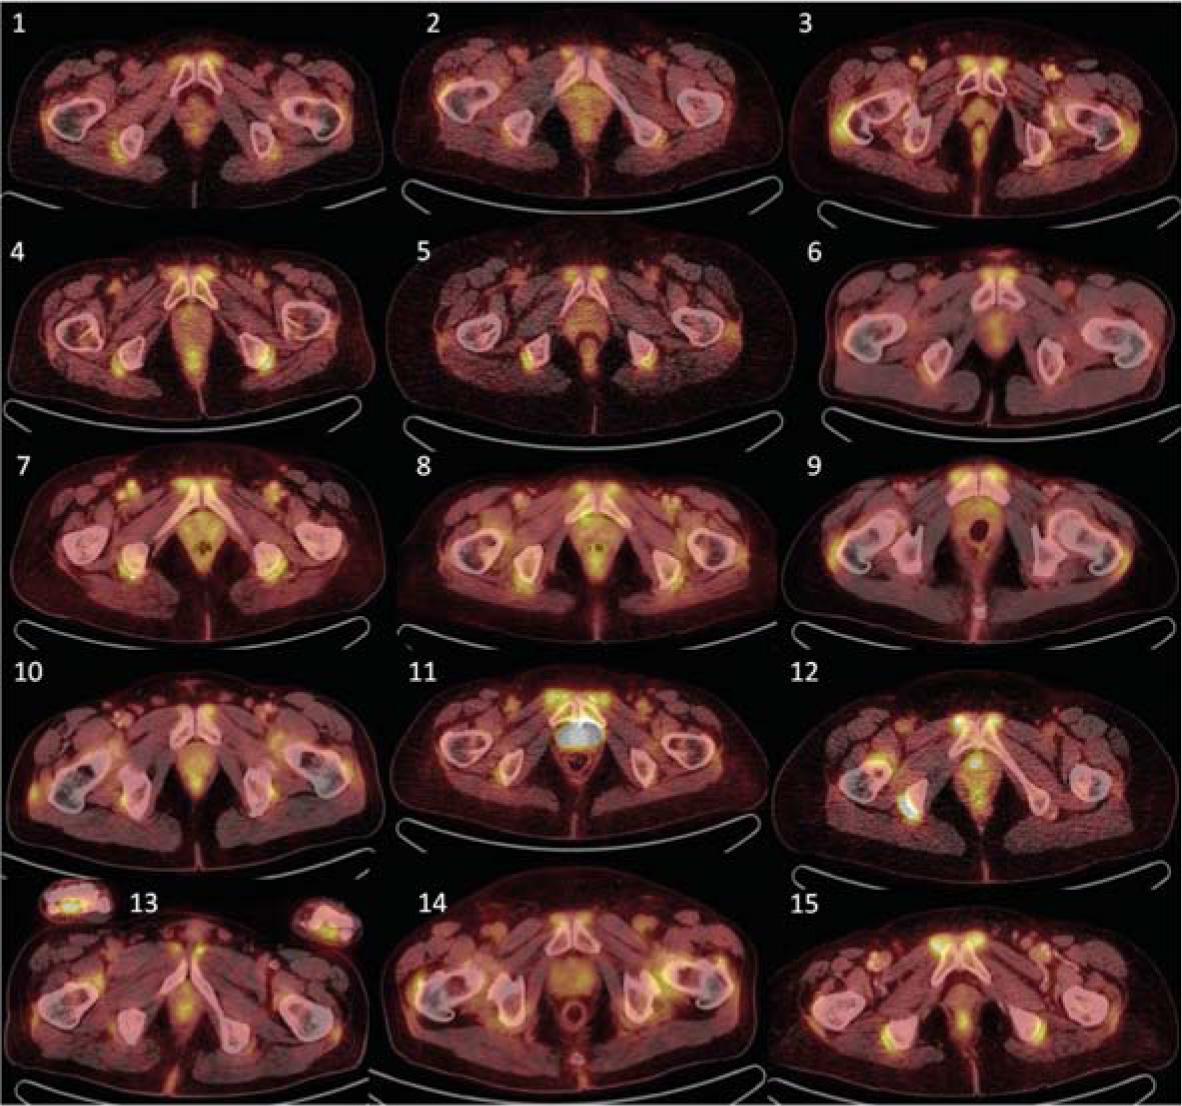

18F-FDG PET/CT characteristic including 18F-FDG dosage are summarized in Table 4. Increased 18F-FDG accumulation (positivity) was observed at baseline in all patients in the praepubic region, with praepubic-to-liver ratios higher than 1.0. This accumulation was obvious by visual evaluation only, as presented in Figure 1, and this finding was always accompanied by additional positivity in 18F-FDG PET/CT scans (Table 1). Other sites with increased accumulation were as follow: around the shoulder girdle in all 15 patients, around the hip girdle in 15 patients, and around sternoclavicular joints in 14 out of 15 patients. 18F-FDG PET/CT positivity was observed also in extraarticular synovial structures, in ischiogluteal bursa in 14 patients and between spinous processes of the vertebrae in 14 patients, most commonly within lumbal region in 13 patients.

Initial 18FDG-PET/CT examination of all 15 examined patients, showing transversal planes through maximal praepubic uptake. Visually detectable accumulation can be observed in all patients.